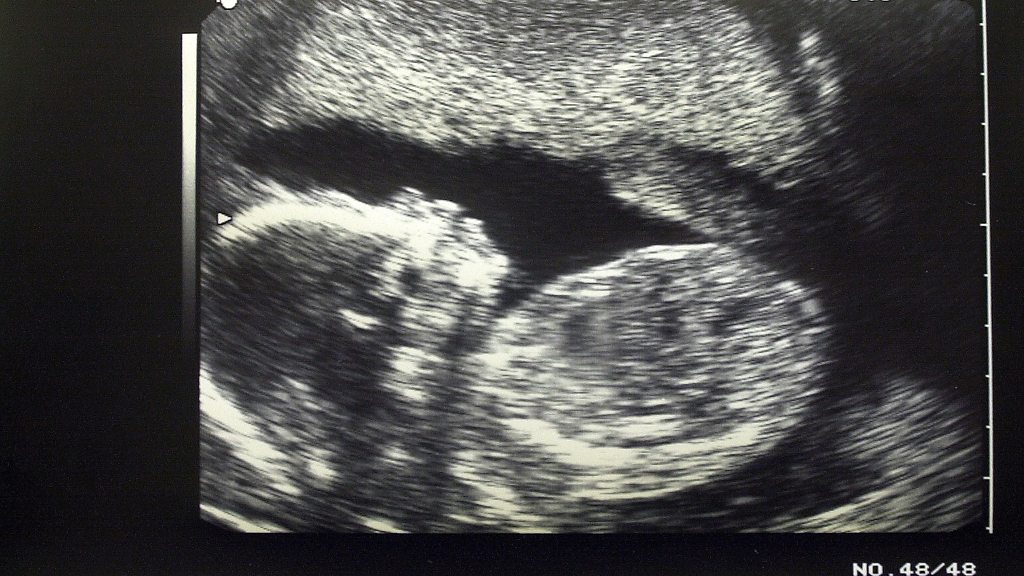

Amanda Benson spoke to Catrin Nye about dealing with Down's Syndrome in surrogacy